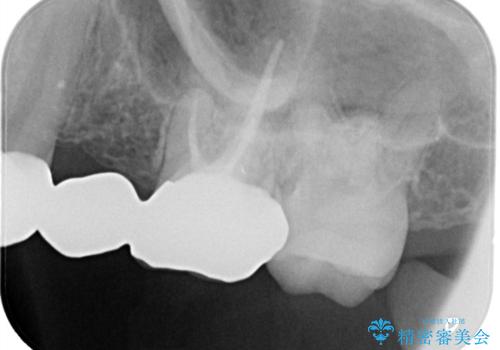

- 保険治療で装着されたかぶせ物と詰め物を変更したいとのことで来院されました。

自然なオールセラミックへ変更することとなりました。

金属を使わないセラミックへ変更することで、自然な見た目になるとともに、ぴったりとした精度の高いかぶせ物を装着することができました。